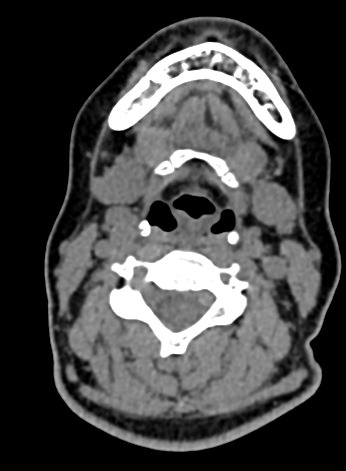

Функциональные пробы подразумевают проведение КТ гортани в трех режимах:

- Пациент делает небольшой вдох, при этом получается КТ- изображение голосовых складок в положении их наибольшего расхождения, что позволяет оценить степень их подвижности и ширину голосовой щели.

- Пациент произносит звук «и». Проба во время фонации позволяет оценить состояние голосовых складок в положении их наибольшего сближения.

- При необходимости проводится проба Вальсальвы (пациент делает глубокий вдох, зажимает нос и рот и делает выдох в носоглотку). Благодаря этому повышается давление в носоглотке и происходит раскрытие грушевидных синусов (пространства в боковых отделах гортани).